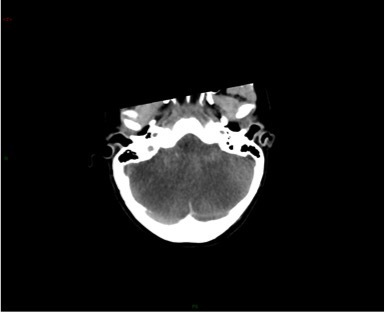

Un scanner cérébral sans injection est réalisé. Les reformations axiales vous sont présentées.

Question 10 : Ce scanner présente :

Les espaces sous sous-arachnoidiens ne sont plus visibles. Ne pas confondre la substance grise qui arrive au contact des os du crâne, avec une hyperdensité spontanée méningée.

Le volume des ventricules paraît faussement augmenté du fait de l’effacement diffus des sillons corticaux.

Qui traduit une augmentation du volume cérébral.

Les sinus veineux sont normalement hyperdenses sans argument pour une thrombose veineuse cérébrale.

Aucun des deux hémisphères cérébraux ne passe sous la faux du cerveau. L’augmentation du volume cérébral est diffuse.

Effacement diffus des sillons corticaux avec début de dédifférenciation des de la substance blanche - substance grise notamment des noyaux centraux. Cela traduit un œdème cérébral diffus secondaire à un bas débit cérébral.